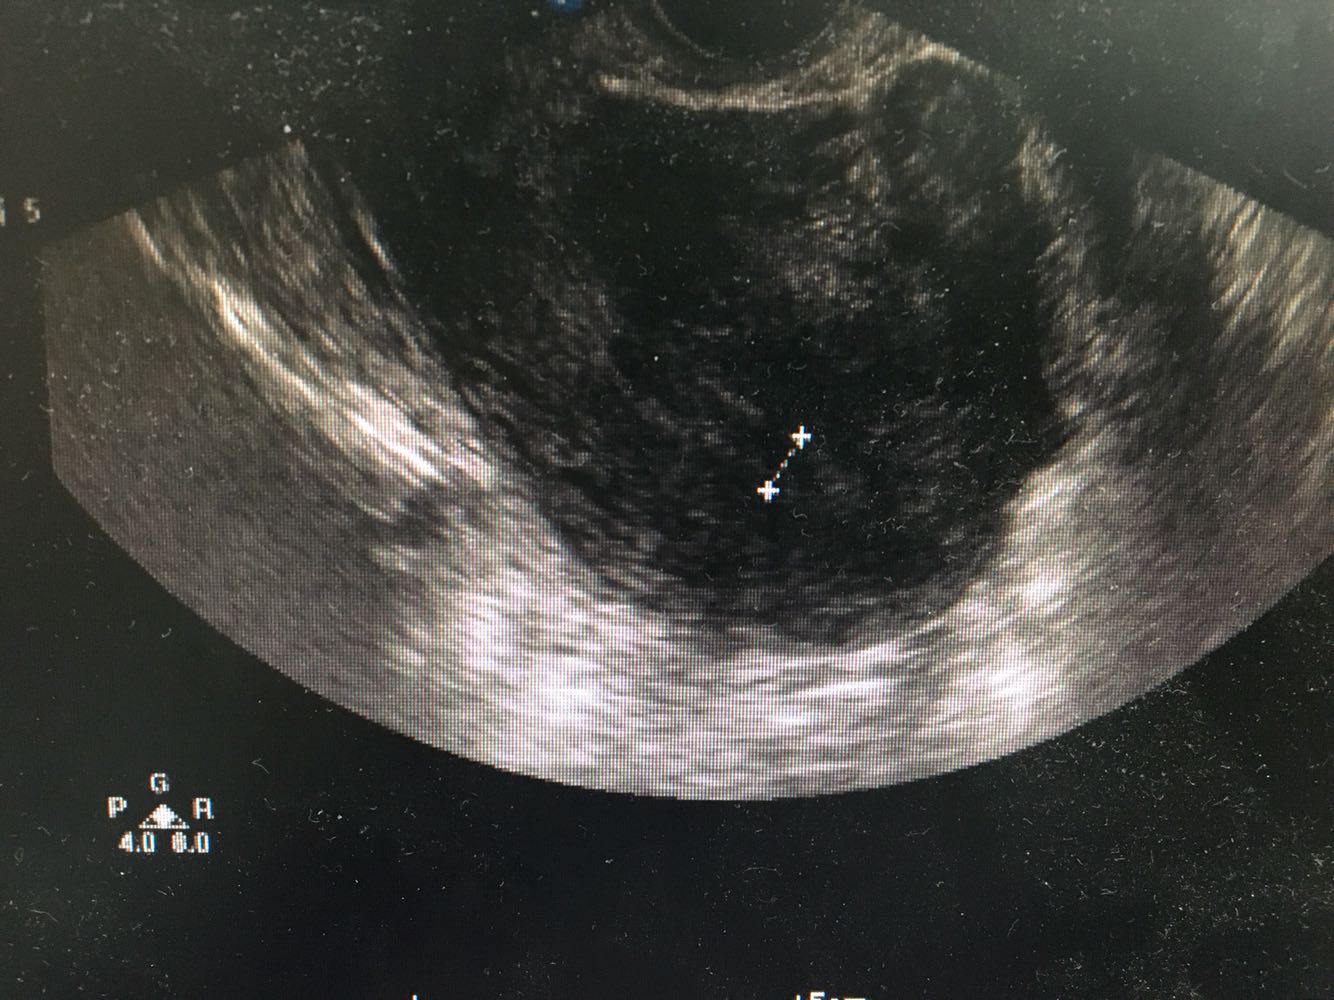

1、患者,女性,55岁 2、主诉:发现子宫肌瘤5年,伴进行性增大伴半年 现病史:1-0-2-1,初潮16岁,平时月经规律,6/28天,量中,痛经(±),LMP:2017-2-13。患者2015年体检时发现子宫肌瘤(具体报告未见),当时月经量无增多,偶伴痛经,偶伴腹胀感,无下腹疼痛感,无头晕乏力,无腰酸背痛,无异常阴道流血流液,存在白带增多伴异味,无尿频尿急。之后定期复查体检发现子宫进行性增大,半年前妇科B超:可见数个最大约67*60*56mm的低回声团块,界清,内部回声不均匀,提示子宫肌瘤,患者自觉尿频,每日小便10多次,夜间小便1次,有尿不净感,偶有腰酸、肛门坠胀感,建议患者手术治疗,为求进一步诊疗,遂就诊门诊,门诊拟“子宫肌瘤”收治。 3、既往史:妇科炎症30余年,白带量多,有异味,否认其他慢性病史